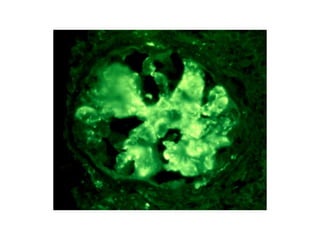

• La afectación renal se manifiesta como consecuencia del

depósito de inmunocomplejos en el interior del capilar

glomerular, la activación del complemento y la liberación

de los mediadores inflamatorios.